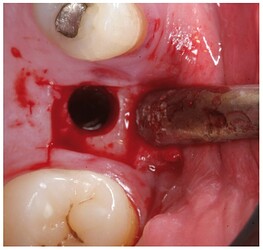

Full thickness flap elevation and preparation of the implant bed with drills and osteotomes

Controlled fracture of the floor of the maxillary sinus using an osteotome.

Insertion of the sinus balloon for detachment of the sinus membrane.

Particulate bone graft placement.

Implant positioned in the same surgical step.